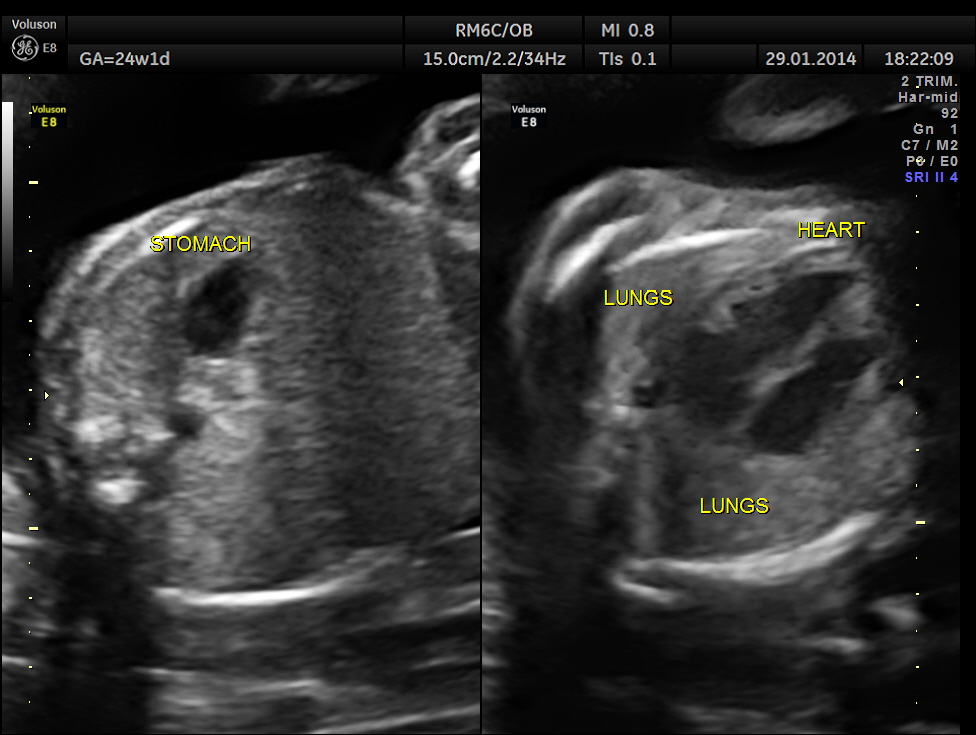

This was a 32-year-old lady – primi gravida . She was referred for an anomaly scan around 24 weeks gestation.Her earlier scan done in the first trimester elsewhere was reported as normal.

Images of the other organs are given below.

In this patient no other associated anomaly could be made out and so she was re assured ; She came for a review 1 month later.